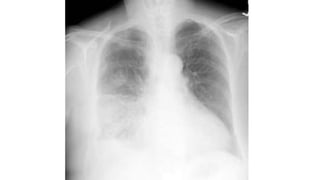

• Mujer de 23 años, infectado con VIH, se presenta al servicio de

urgencias con antecedente de 5 días con fiebre y tos productiva.

• Actualmente se encuentra con terapia antiretroviral, y su conteo de

CD4 es de 300/mm³. Su temperatura es 39 C, pulso 95/min, 22

respiraciones por minuto, presión arterial de 115/76.

• El examen físico revela matidez a la percusión estertores en la base

del pulmón derecho.

• Se obtiene la siguiente radiografía.